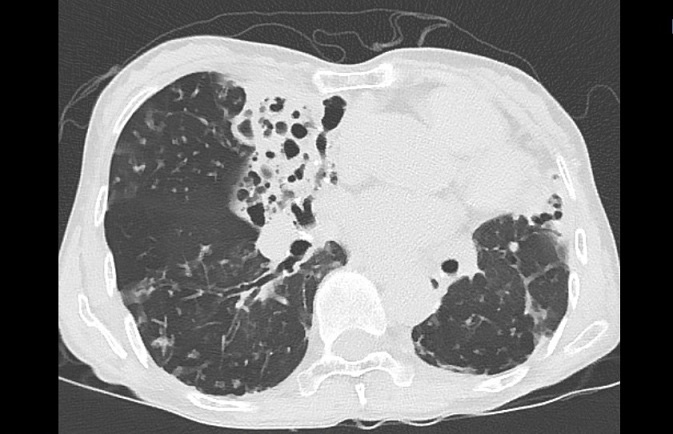

기관지확장증의 CT 사진